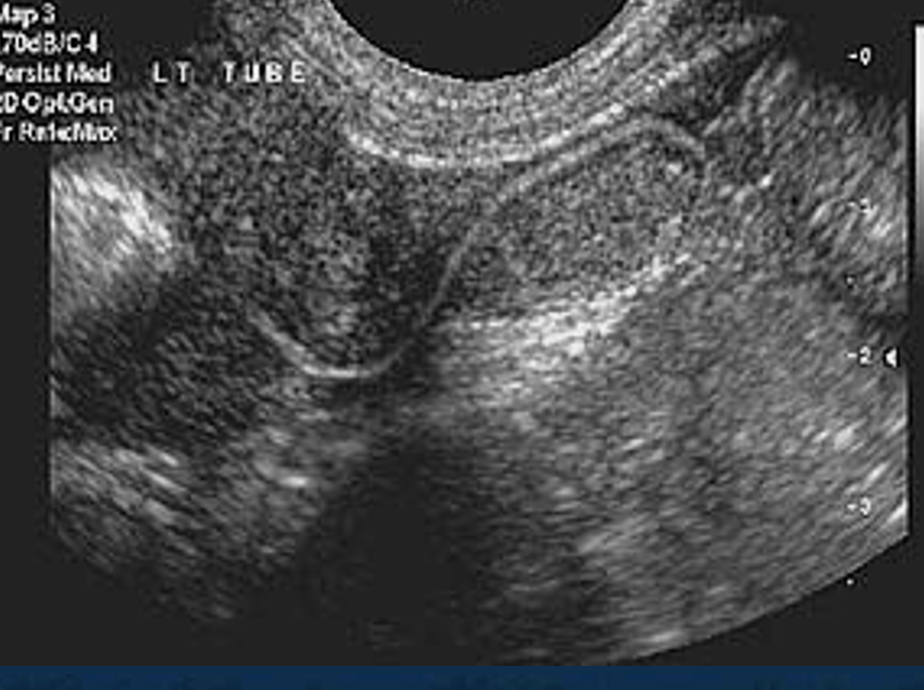

HyCoSy (Ultrasound & Dye) test

Hysterosalpingo Contrast Sonography

-This is an alternative for HSG.